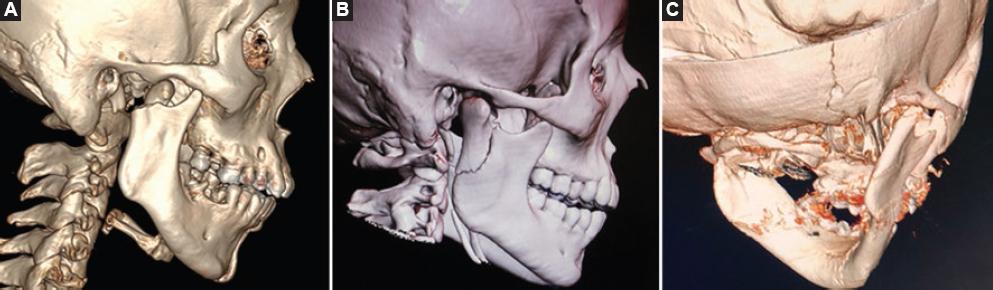

There are various designs of plates as osteosynthesis material used to perform the internal fixation. The five main designs for performing osteosynthesis, as required on a case-by-case basis, are: (1) straight standard plate, (2) inverted Y plate, (3) delta plate, (4) trapezoidal plate, and (5) rectangular plate. The use of each of them depends on the fracture to be reduced, being the straight plate the most used, due to its high resistance29,30 (Fig. 3). Strut plates are also a three-dimensional plate option for transoral endoscopically assisted approaches, providing intraoperative handling and fitting accuracy, precluding complications such as plate fatigue fractures31.